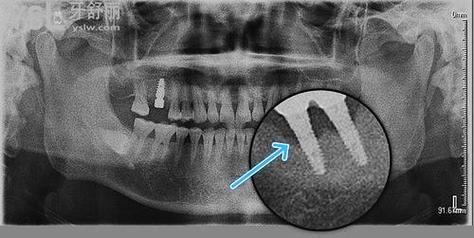

- 种植体位置偏差:若种植体植入时过于靠近邻牙牙根,可能压迫牙根或导致骨吸收,引发邻牙倾斜。

- 邻牙牙根吸收:极少数情况下,种植手术可能损伤邻牙牙根(如种植体位置过近),导致牙骨支持不足,引发倾斜。

- 种植体位置规划:保持与邻牙牙根至少1.5mm安全距离,避免邻侧骨板穿孔。